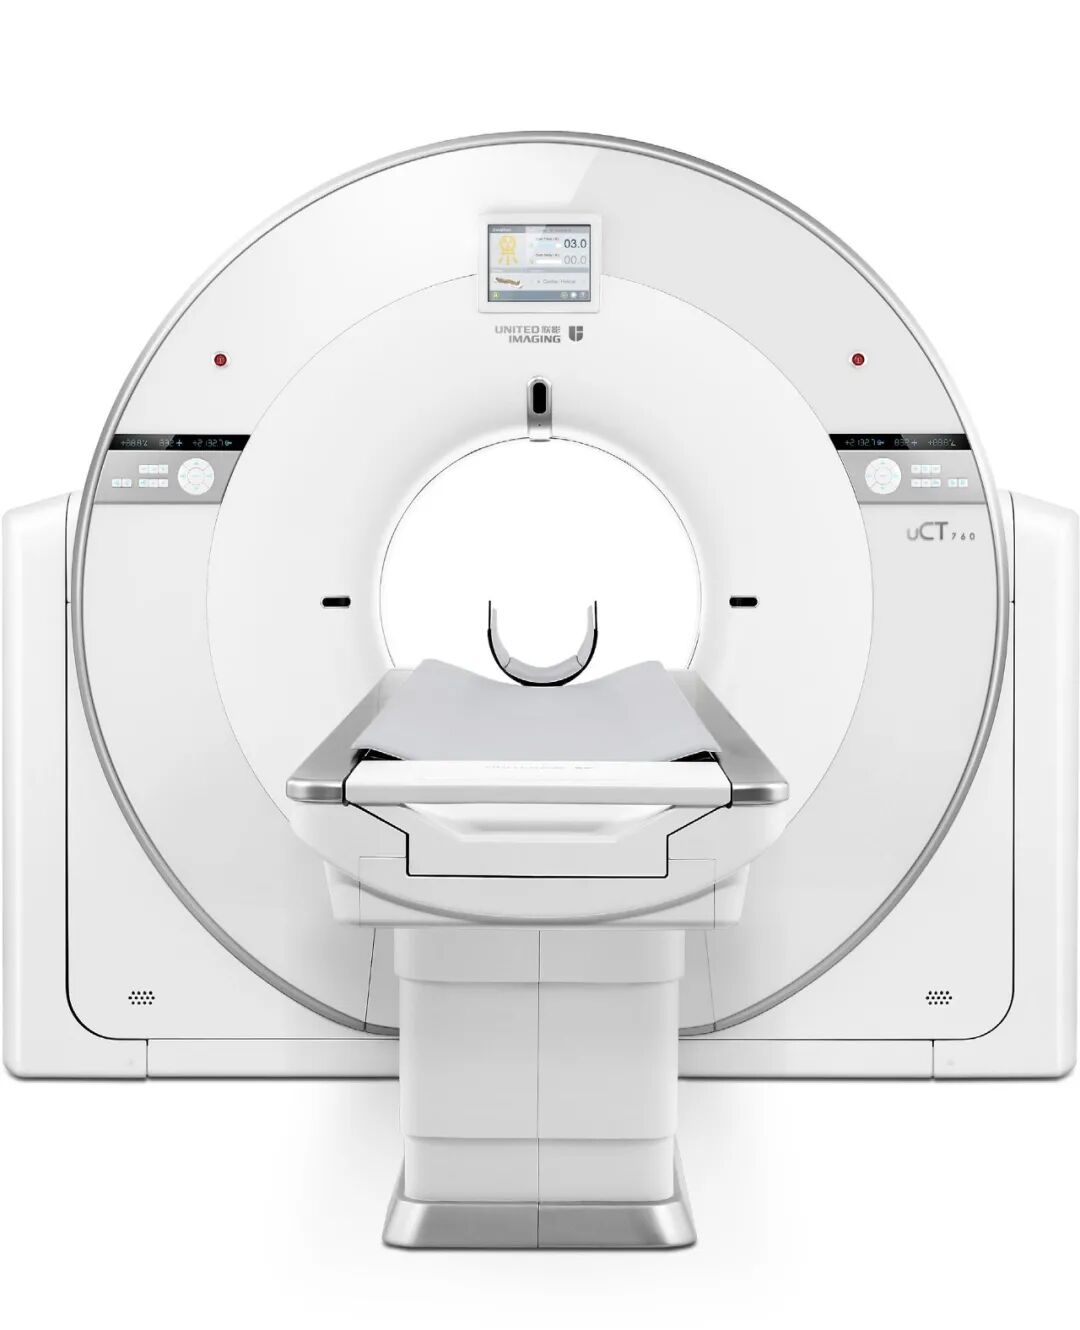

在西双版纳州委、州政府、勐腊县委、县政府大力支持下,勐腊县人民医院最新引进了上海联影医疗科技有限公司自主研发生产的高端128层螺旋CT(产品型号:uCT 760)正式投入使用,标志着我院的诊疗水平又上升一个新的台阶。

▲高端128层螺旋CT(型号:uCT 760)